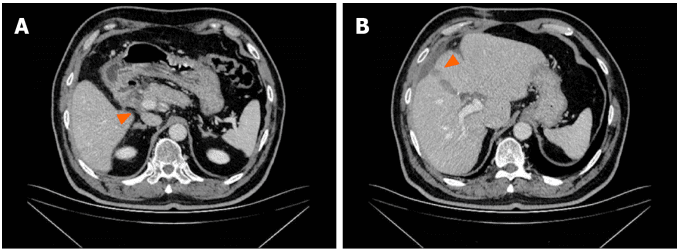

3 个周期的治疗后,CA19-9 水平降至 11.4 U/mL。MCCT 显示肝十二指肠系膜淋巴结数量减少,肝 S4 段低密度灶缩小(图 2)。由于治疗效果良好,患者继续进行治疗。

图 2. GC-D 方案治疗 3 个周期后 MCCT 检查结果

(A:肝十二指肠系膜淋巴结缩小;B:低密度灶缩小)